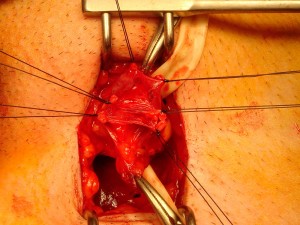

La magnificación que nos ofrecen las gafas (cuatro aumentos) nos permite: identificar la arteria y no dañarla, localizar los linfáticos y no ligarlos y ver con claridad todas las venas, separarlas con cuidado y ligarlas para corregir la dilatación varicosa (varicocele).

Figura 3. Visión del cordón inguinal con sus múltiples estructuras.

A continuación y con la ayuda de las gafas lupa (cuatro aumentos) identificamos la arteria testicular para no lesionarla. Localizamos los linfáticos para no ligarlos y provocar complicaciones (hidrocele). Posteriormente, con mucho cuidado vamos disecando (liberando) todas la venas y las vamos ligando y seccionando. Al final de la cirugía, todas las venas deben estar ligadas y seccionadas (así se evita el reflujo de sangre desde riñón al testículo) y la arteria testicular, los linfáticos y el deferente deben estar preservados.